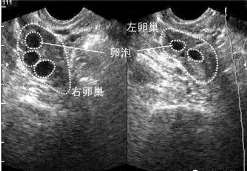

查看全文可否治疗多囊卵巢怀孕。可以做试管吗 多囊卵巢综合征的治疗包括:1。一般治疗:应积极运动,减少高脂高糖食物的摄入 […]